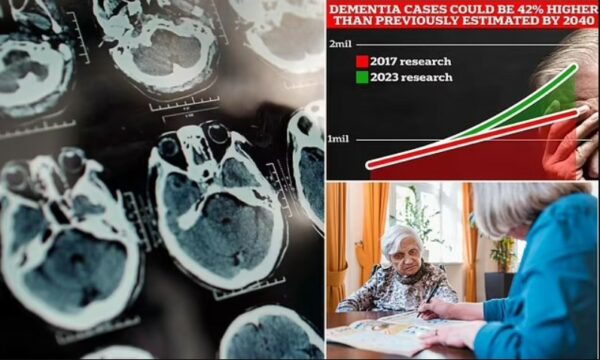

Shkencëtarët e njohur zbulojnë shenjat më të hershme të demencës që nuk lidhen me kujtesën

Shkencëtarët zbulojnë se një dietë e njohur ul rrezikun e demencës

Vetëm 16 gllënjka kafe në ditë mbron nga demenca

Shenja e parë e fshehtë e demencës që mund të shfaqet 20 vjet përpara simptomave të zakonshme

Zakoni fizik që mund të nxisë demencën – pavarësisht sa shumë ushtrime bëni

Shkencëtarët e njohur zbulojnë shenjat më të hershme të demencës që nuk lidhen me kujtesën

Shenja e parë e fshehtë e demencës që mund të shfaqet 20 vjet përpara simptomave të zakonshme

Zakoni fizik që mund të nxisë demencën – pavarësisht sa shumë ushtrime bëni

Një ekspert tregon një shenjë të demencës tek të rinjtë – s’është humbja e memories